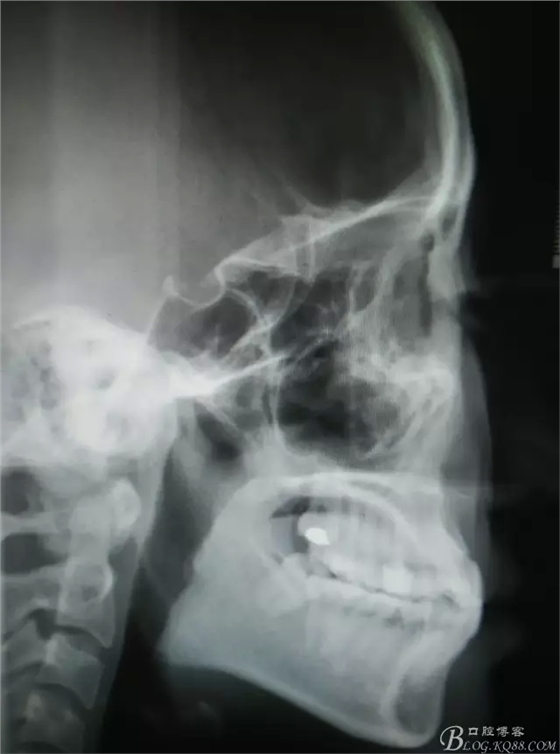

圖1.患者術(shù)前的全景片、側(cè)位片影像檢查:45牙根位于44與46之間,44與46鄰接緊密